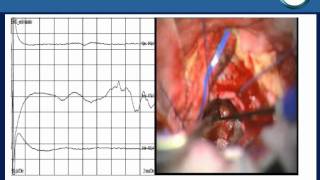

WebPor lo general, la sintomatología del neurinoma del acústico va manifestándose lentamente, por lo que pueden pasar varios años antes de comenzar: Adormecimiento o. WebCirugía del neurinoma del acústico . Por Dr. Roberto Martínez Álvarez 2023-03-10 . La radiocirugía es una de las mejores opciones para los pacientes que sufran Neurinomas. WebMi nombre es Francisco Sánchez Llorente, soy médico, vivo en Málaga y tengo 69 años. En marzo de 2006 me diagnosticaron un neurinoma del acústico de 3 cm de diámetro, y.

WebEl tratamiento de neurinomas del acústico puede variar según: El tamaño y el crecimiento del neurinoma del acústico. Tu salud general. La gravedad de los. WebEl neuroma acústico, cuyo nombre más exacto es schwannoma vestibular, es un tumor benigno que crece en los nervios del equilibrio y la audición. Esos nervios. WebEsquema de su relación con los vasos sanguíneos y los pares craneales. 2019 Christian Iorio-Morin, Roman Liscak, Vilibald Vladyka, Hideyuki Kano, Rachel C Jacobs, L Dade.